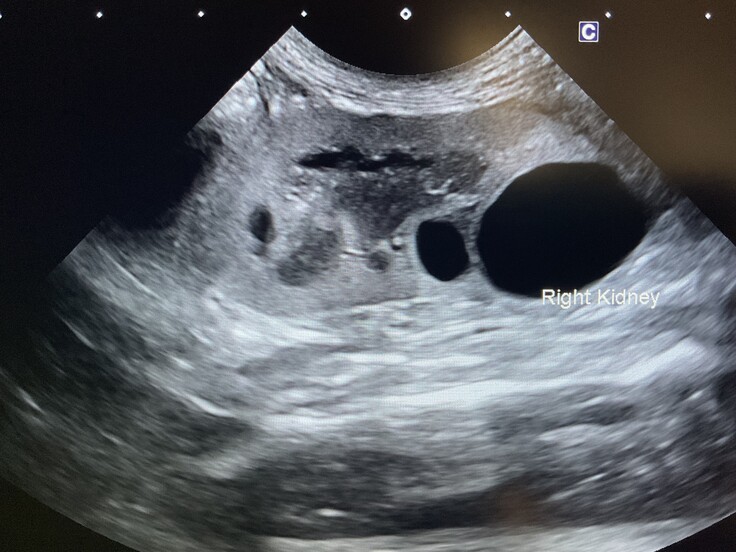

※病院での検査結果

・推定年齢:10歳

・骨盤骨折

・両腎嚢胞

・貧血、低アルブミン、白血球数上昇

・重度のノミ感染

・歯周病、歯石

・エイズ白血病:陰性

夜間にミケコちゃんを見ていたため分かりませんでしたが、左耳に小さな耳カットがあり、避妊手術済であることが判明しました。また、愛護センターに確認したところ、該当する迷子届けは出ていませんでした。

診断結果から、今後も腎臓や口腔の治療が必要になる見込みです。